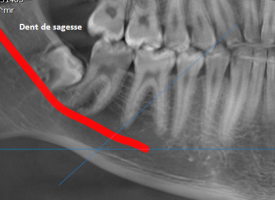

Cet état de fait doit normalement alarmer tout le monde. Le patient comme le chirurgien-dentiste traitant. Un diagnostic parodontal rapide doit être entrepris (à l’aide principalement d’une radiographie spécifique nommée bilan long cône).

En effet, des dents mobiles et/ou qui ont changées de place (généralement qui » partent en éventail » sur les dents du haut et de devant) ainsi que des rougeurs/gonflements des gencives accompagnées de saignement et d’une mauvaise haleine (ou d’un mauvais goût en bouche) sont les signes inconstants (pas toujours présents) de la maladie parodontale (déchaussement dentaire).

Lorsque ces signes sont importants il est souvent trop tard d’où l’intérêt d’avoir un suivi sérieux régulier chez son chirurgien-dentiste qui lui même doit s׳efforcer de faire réaliser des radiographies régulièrement pour contrôler la physionomie de l’os sous-jacent aux dents.